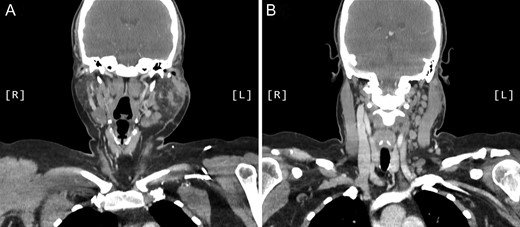

A computed tomography (CT) scan demonstrated left parotid multifocal soft tissue abnormality and enlarged left-sided cervical lymph nodes, with prominent superficial left supraclavicular fossa lymph nodes (Figs 3 and 4).

Coronal CT sinuses (with contrast) showing left parotid multifocal soft tissue abnormality (A) with enlarged left-sided cervical and superficial supraclavicular fossa lymph nodes (B).